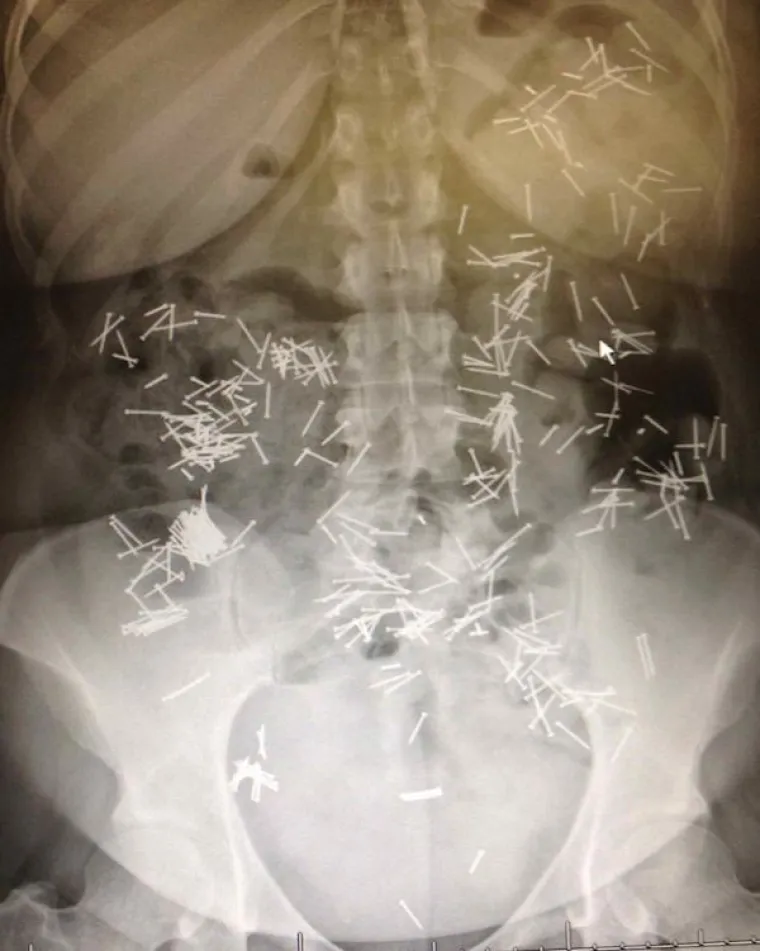

Čavli.